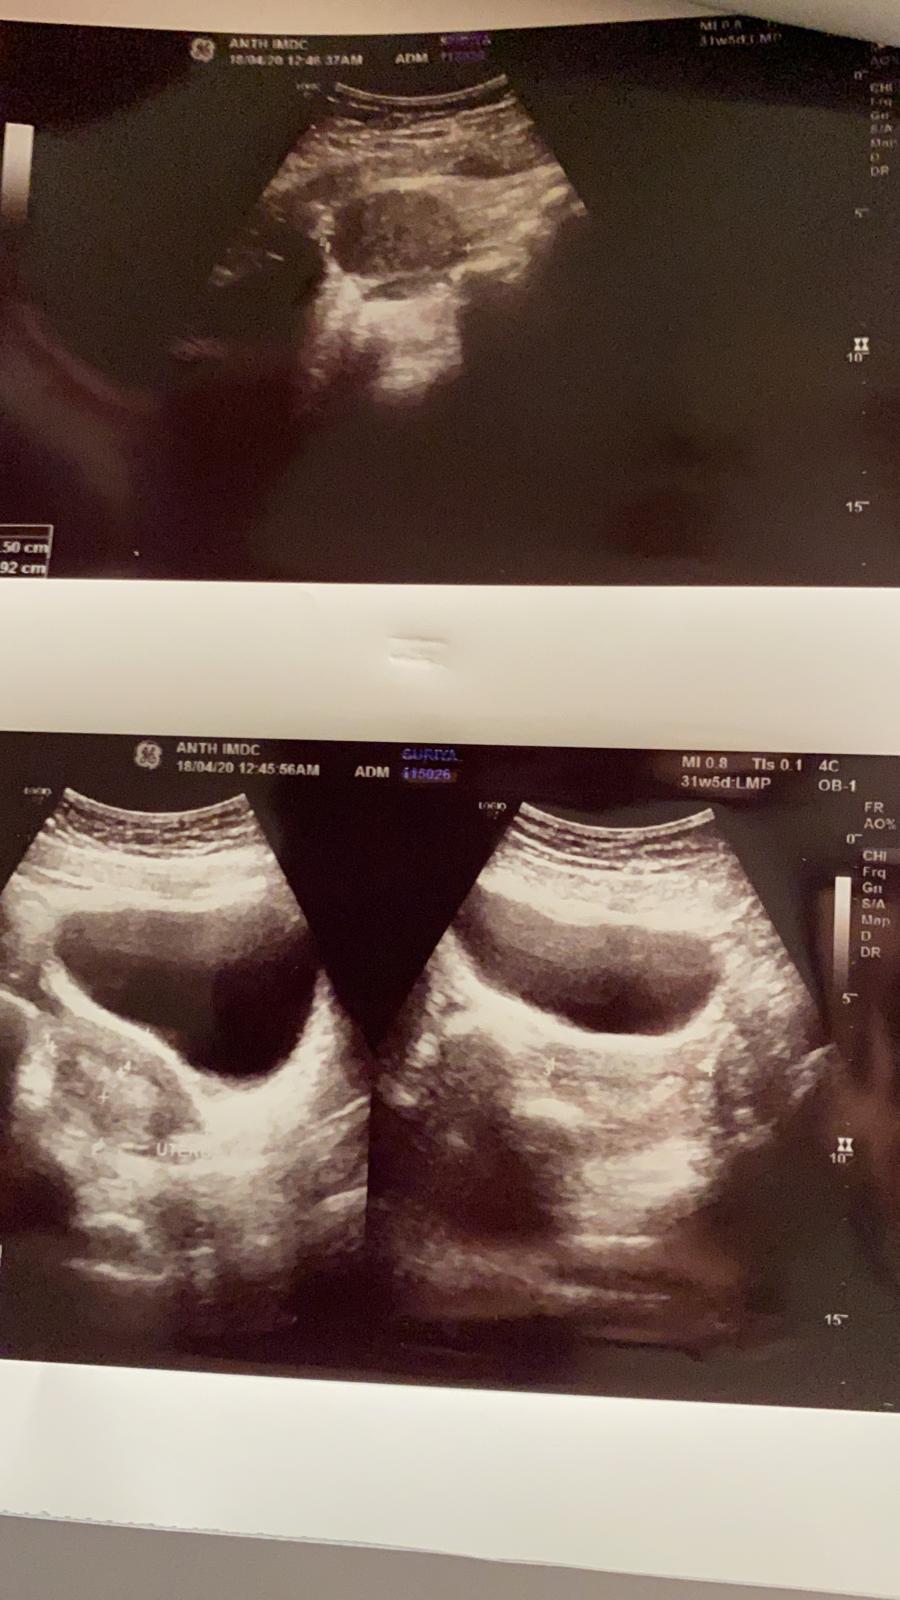

Had a miscarriage. They are saying i probably have a cyst. I did not do a pregnancy test before so i am not sure whether i was pregnant or is the bleeding coming from the cyst rupture please see report

u should go for serum beta HCG test to ruleout the cause of bleeding.

Get beta hcg done and where is written report

Please attach written report